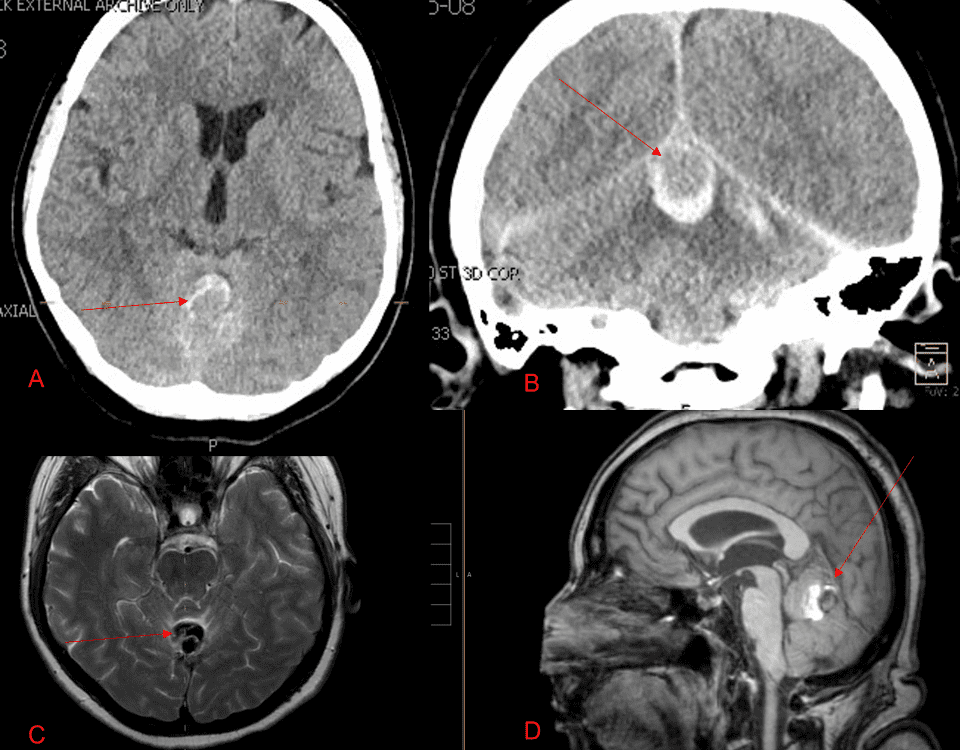

August 29, 2022

A 55-year-old woman presented with acute onset of severe headache, and possible witnessed seizure. Imaging confirmed intraventricular hemorrhage primarily focused within the fourth ventricle with diffuse […]